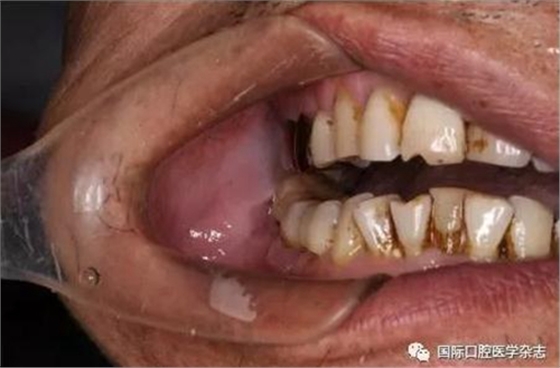

A:術前開口度;B:術后開口度;C:術前影像學檢查片;D:術后影像學檢查片。

圖 19 關節(jié)成形術前后對比

3.1.4 顳下頜關節(jié)內強直的手術治療 顳下頜關節(jié)成形術[18-19](圖19)。